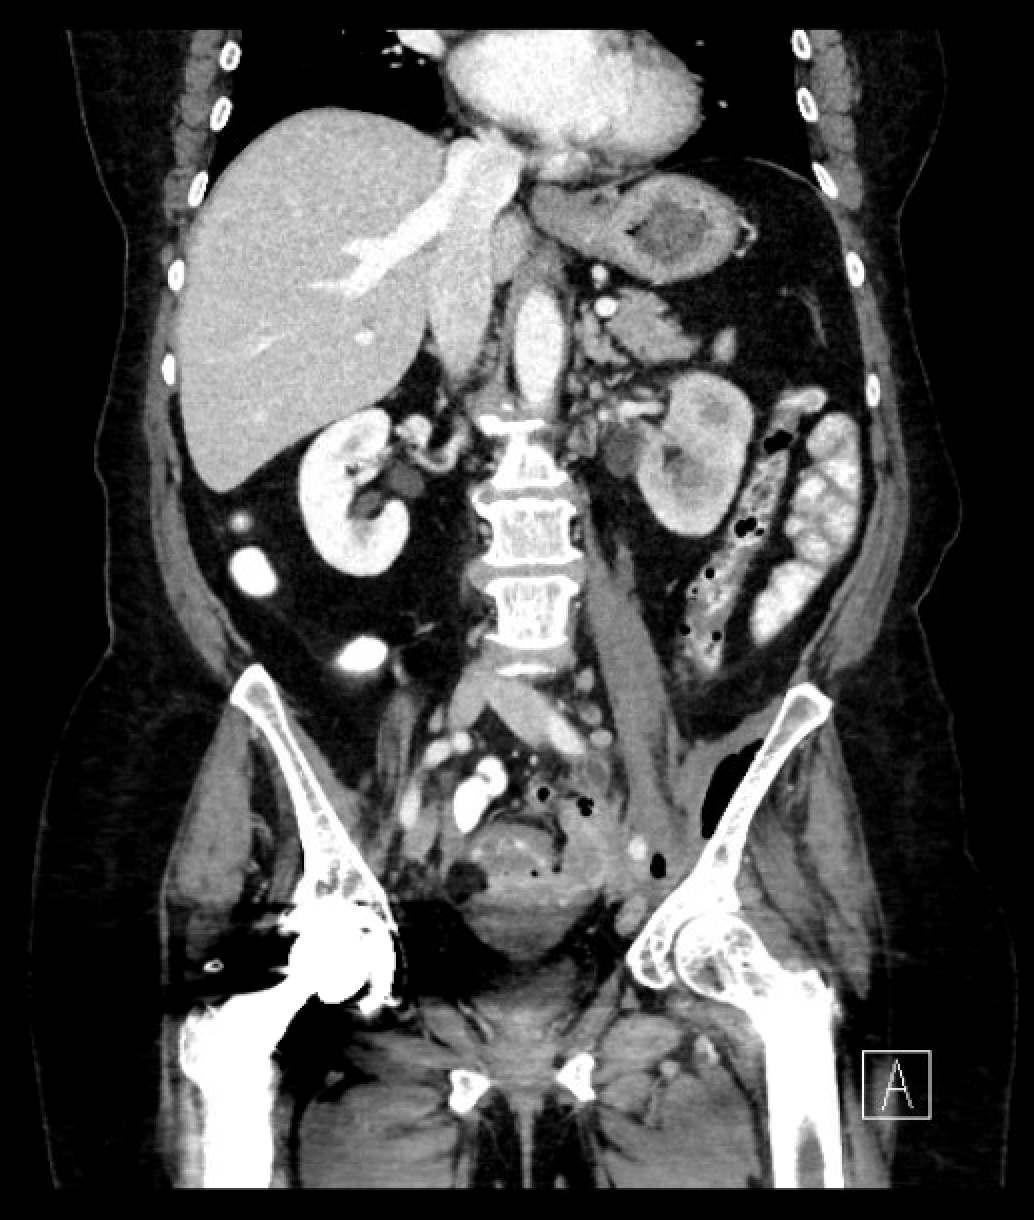

Coronal view of sigmoid to iliacus muscle fistula with air seen within the iliacus muscle.